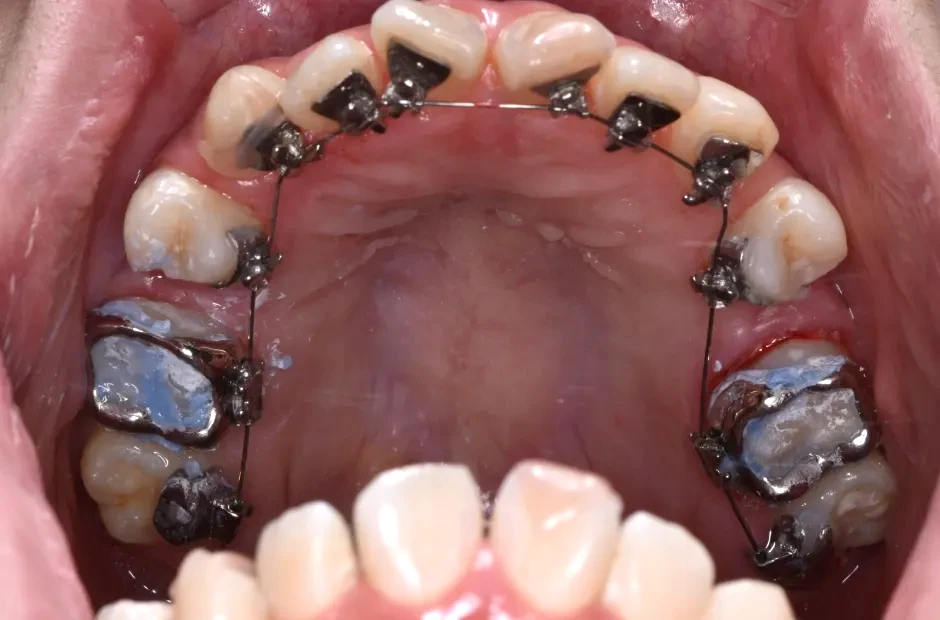

治療症例

ブラケット矯正

前歯部反対咬合

| 診断名・主訴 | 前歯部反対咬合 |

|---|---|

| 年齢・性別 | 14歳・男性 |

| 治療期間・回数 | 1年2か月 |

| 治療に用いた主な装置 | ブラケット矯正 |

| 抜歯部位 | なし |

| 治療費 | 60万円(税抜) |

| リスク・副作用 | 装置による違和感・疼痛・歯肉退縮・歯根吸収・虫歯のリスクなど |

治療中